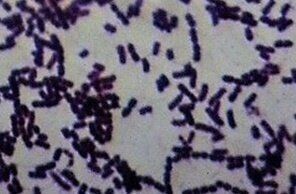

病原体であるコリネバクテリウム属菌(写真提供/斉藤動物病院院長 齊藤邦史先生)

感染した犬や猫との接触、飛沫などから感染します。海外では殺菌処理されていない生乳を摂取することで感染したケースも。人・犬ともにクシャミ、鼻水、発熱など風邪に似た症状に始まり、咽頭痛やセキのほか、ジフテリアと似た症状を引き起こします。重症化すると呼吸困難により死亡する例も。人から人への感染はなく、感染者の多くは高齢者であると報告されています。